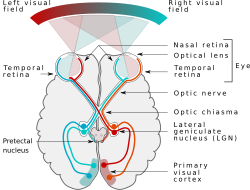

Koʻrish organlari - odam va hayvonlarning yorugʻ sezadigan organlari. Barcha umurtqali va koʻpchilik umurtqasiz hayvonlarda boʻladi. Koʻp hujayrali hayvonlar Koʻrish organlarining asosiy elementi sezgir hujayralar — fotoretseptorlar hisoblanadi. Ularning periferik (chetki) uchi yorugʻlikni qabul qiladi. Fotoretseptorlar umurtqali hayvonlarda qadahcha yoki tayoqcha shaklida. Koʻrish organlari koʻpchilik hayvonlarning boshida joylashgan boʻlib, koʻrish nervlari orqali bosh miya bilan bogʻlangan. Oddiy Koʻrish organlari epiteliy hujayralari orasida joylashgan ayrim koʻrish hujayralaridan iborat (mas, yomgʻir chuvalchanglari). Oddiy Koʻrish organlari faqat yorugʻlikni sezadi, buyumlarni farq qilmaydi. Evolyasiya jarayonida tarqoq koʻrish hujayralari bir joyga toʻplanib, teri ostiga botib kirishi, pigment ekranlari, yorugʻlikni sindirib toʻr qavatga tushiradigan, akkomodatsiyalovchi, koʻzni harakatlantiruvchi, uni muhofaza qiluvchi va boshqa moslamalar paydo boʻlishi tufayli Koʻrish organlari mukammallashib borgan. Ayrim boʻshliqichlilar, tuban chuvalchanglar, bir hujayralilarda Koʻrish organlari oddiy koʻz dogʻlaridan iborat. Keyinchalik koʻrish dogʻlari takomillasha borib, pufaksimon yoki qadahsimon shaklga kiradi (baʼzi boʻshliqichlilar va mollyuskalar), pufak yorugʻlik sindiruvchi dirildoq shishasimon tana bilan toʻla boʻladi. Koʻpchilik boʻgʻimoyoqlilarning Koʻrish organlari fasetkali koʻzdan iborat. Faset-kali koʻz narsalar shaklini farq qiladi. Odamlar va umurtqali hayvonlar, baʼzi umurtqasizlar (boshoyoqli mollyuskalar) koʻzi ayniqsa yaxshi rivojlangan boʻlib, kamerali koʻzlar deyiladi.

- Koʻrish nervi